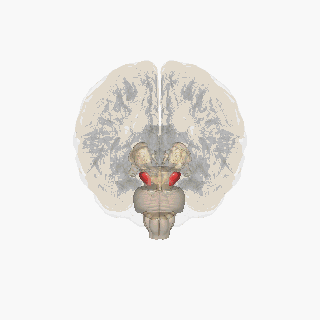

Substantia nigra highlighted in red. | |